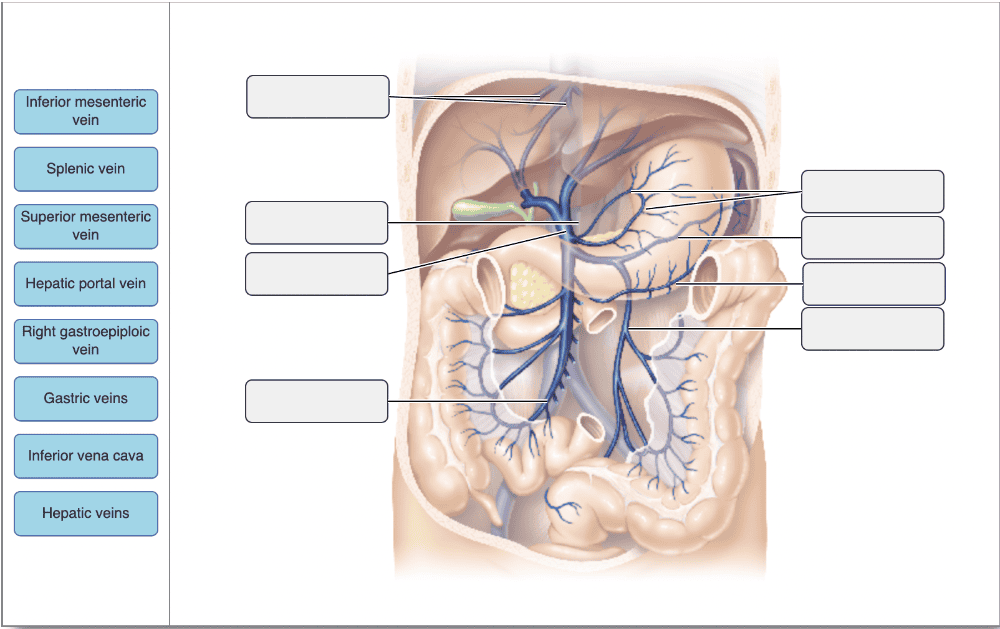

Drag the appropriate labels to their respective targets.

Drag the appropriate labels to their respective targets.